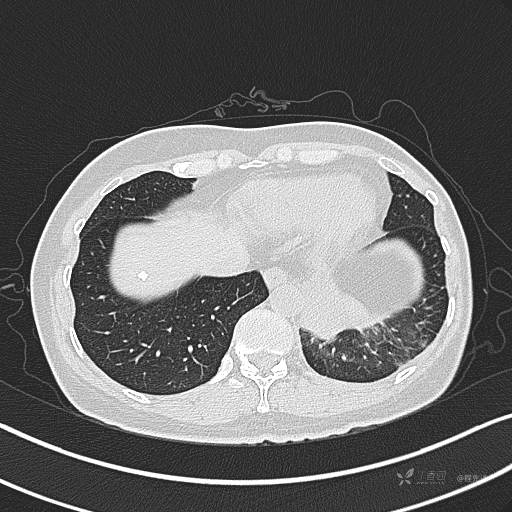

增强动脉期

动脉期CT值约74HU